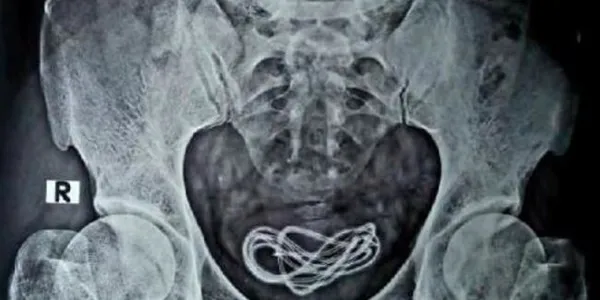

Hindistan'da tıp dünyasını şaşkına çeviren bir olay yaşandı. Olay, Hindistan'ın Assam eyaletindeki Guwahati kentinde meydana geldi. 30 yaşında olduğu belirtilen bir kişi, karın ağrısı şikayetiyle hastaneye gitti. Çekilen röntgende, kişinin mesanesinde yaklaşık bir metre uzunluğunda bir şarj kablosunun olduğu görüldü.

Hindistan medyası, karın ağrısı şikayetiyle hastaneye giden kişinin doktorlara, "Şarj kablosunu yuttum" dediğini duyurdu. Doktorlar ameliyat sırasında şarj kablosunun, kişinin cinsel organından mesanesine girdiğini tespit etti. Ameliyatı gerçekleştiren Dr. Walliul Islam, "Yaklaşık 25 yıldır cerrahım ancak şu ana kadar bir ameliyatta ilk kez böyle bir durumla karşılaştım" dedi.